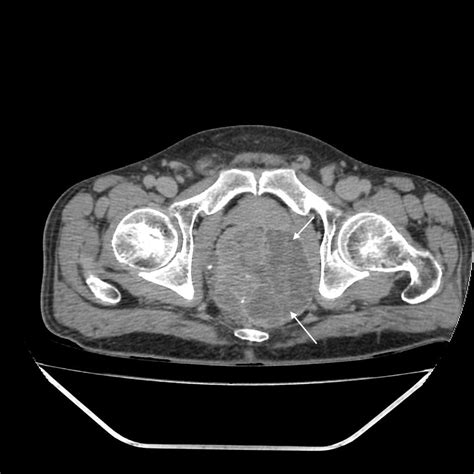

Diagnosing a perianal abscess typically involves a physical examination by a healthcare provider. The doctor will examine the affected area and may ask about symptoms and medical history. In some cases, additional tests may be necessary to confirm the diagnosis or rule out other conditions. These tests may include:

• Imaging Tests: Such as an ultrasound or CT scan to visualize the abscess and surrounding tissues.

Perianal Abscesses Pictures

Visual aids can be incredibly helpful in understanding medical conditions. While it’s important to note that viewing perianal abscesses pictures can be graphic and may not be suitable for all audiences, they can provide a clear understanding of what these abscesses look like. These images often show the redness, swelling, and drainage associated with the condition. If you are considering viewing such images, it is advisable to do so under the guidance of a healthcare professional.